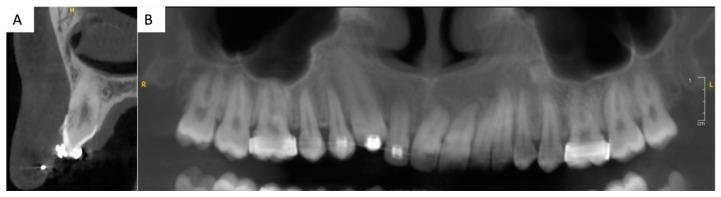

As the functional and aesthetical importance of the canine cannot be overstated, the management of a missing canine is challenging. This case report describes the treatment of an infra-occluded ankylosed maxillary canine in a patient with previously failed orthodontic treatment. A 20-year-old patient sought a second opinion for orthodontic treatment failure. The patient presented with an impacted, ankylosed, and severely infra-occluded right maxillary canine, as well as an iatrogenic clockwise cant of the maxillary occlusal plane and several root resorptions. The treatment corrected the cant of the occlusal plane while avoiding further root resorption, partially extracted the upper right canine, improved the quality and quantity of the soft tissue in the newly edentulous area, and provided a prosthetic rehabilitation using a lithium disilicate ceramic resin-bonded cantilever bridge. The use of a cantilevered bridge resulted in an aesthetically pleasing and minimally invasive rehabilitation. This technique is reversible, does not affect pulp vitality, and is a viable solution for rehabilitating the smiles of young patients. The smile rehabilitation for an ankylosed maxillary canine, especially in the case of a previously failed orthodontic treatment, is an important clinical challenge. A minimally invasive long-term restoration with a cantilever bridge is a viable solution. Functional and aesthetically pleasant results can be achieved with a multidisciplinary approach.

由于尖牙在功能和美学方面的重要性再怎么强调也不为过,因此处理缺失的尖牙具有挑战性。本病例报告描述了一名正畸治疗失败患者的上颌骨粘连性低位阻生尖牙的治疗情况。一名20岁患者因正畸治疗失败寻求二次诊断。患者表现为右侧上颌骨尖牙阻生、粘连且严重低位,上颌咬合平面医源性顺时针倾斜,并有多处牙根吸收。治疗纠正了咬合平面的倾斜,同时避免进一步的牙根吸收,部分拔除右上尖牙,改善了新缺牙区软组织的质量和数量,并使用二硅酸锂陶瓷树脂粘结悬臂桥进行了修复。使用悬臂桥修复在美学上令人满意且微创。该技术是可逆的,不影响牙髓活力,是修复年轻患者笑容的可行解决方案。对于粘连性上颌尖牙的微笑修复,尤其是在正畸治疗先前失败的情况下,是一项重要的临床挑战。采用悬臂桥进行微创长期修复是一种可行的解决方案。通过多学科方法可以实现功能和美学上令人满意的效果。